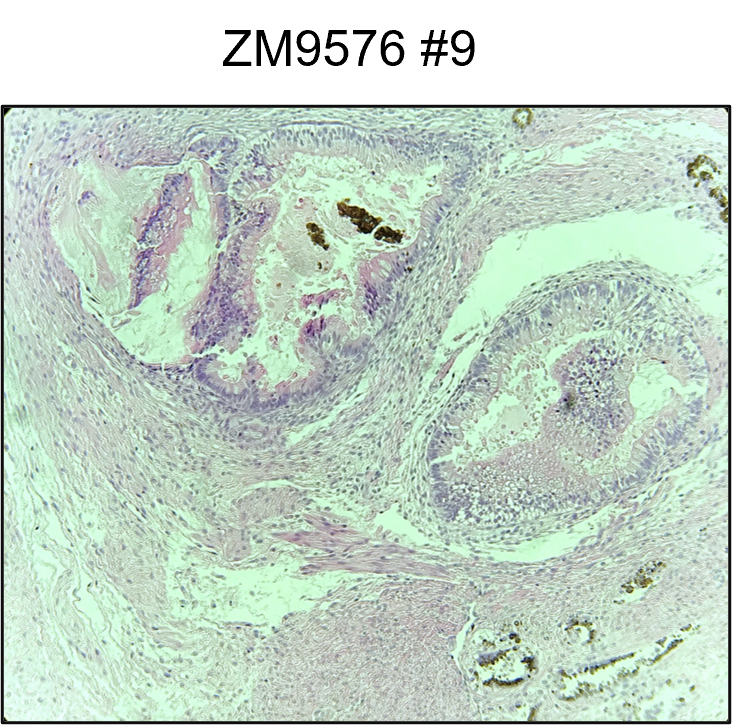

ZM9576 #9, ASupd3

| hPSCreg name | YUi011-A |

Teratoma assay

Immunofluorescence staining of OCT4, NANOG, Tra-1-60, SSEA-4